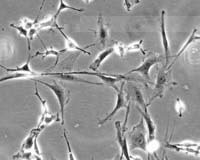

Doctor injecting patients with stem cells

disclaimer: image is for illustration purposes only